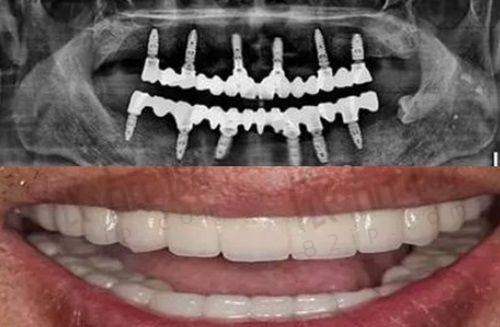

肖求义医生擅长的口腔项目较多,在种植牙修复、全瓷牙美学修复以及青少年和成年人牙齿固定矫正技术方面优势明显,是一位非凡的综合口腔医生。他尤其在牙齿种植和矫正技术上,深受众多顾客的喜爱与选择。从业期间,他多次参加国内外的口腔学术交流会议,有一定的进修和学习经历。因此,在口腔诊疗手术中,他能更好地了解顾客的口腔牙齿需求,使预期成效与实际手术成效高度相符,其口腔技术值得信赖。有顾客评价:“医生的服务态度和蔼且有耐心,会详细介绍情况,精心解决问题。”

该院的牙齿矫正技术特别受欢迎。在制定手术操作方案时,能根据顾客不同的牙齿畸形情况进行个性化制定,可操作性强。手术由经验多的牙齿矫正医生亲自操作,无菌环境有保护。而且院内拥有众多有名的牙齿矫正器品牌授权,能从根本上提升口腔诊疗手术的质量,广大顾客可以放心选择。